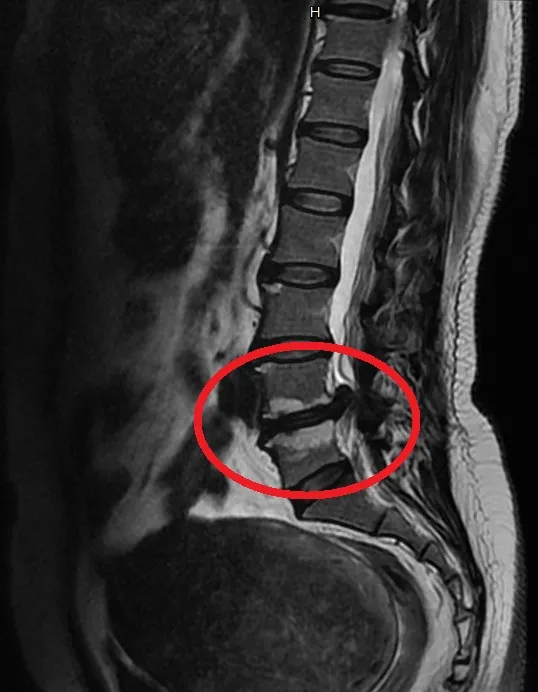

核磁共振顯示腰椎第四五節間有椎間盤突出。

54歲的楊女士是一名居家照護員,某日她在工作時突感右側屁股劇烈疼痛,疼痛向下延伸至大腿和小腿的外側,走路都需要人幫忙攙扶。經X光及核磁共振檢查,顯示腰椎有骨刺及第四、五節椎間盤突出,為了能快速地回到工作,她選擇「脊椎內視鏡椎間盤切除」手術。手術完成後當天即表示屁股及大腿都不痛了,第二天就出院返家,之後順利回到工作崗位。

長安醫院骨科喻大久醫師指出,照護員的工作性質常需要彎腰、搬動病患,對腰椎構成極大壓力,長時間下來容易引發椎間盤突出。因楊女士的第四、五節椎間盤突出造成右側脊髓空間狹窄,儘管經過藥物和復健治療,但是因為神經壓迫嚴重,造成的疼痛仍持續影響她的生活和睡眠,並影響到走路功能,最終決定進行內視鏡手術。